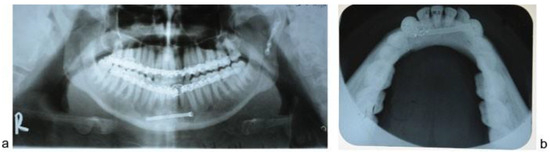

Figure 8. Case 2: Preoperative CT scan of axial section showing interforaminal fracture of left side mandible.

Figure 10. Case 1: Preoperative orthopantomograph showing interforaminal mandible fracture of right side.

Figure 12. Case 2: Preoperative orthopantomograph showing interforaminal mandible fracture of left side.

Figure 13. (a) Case 2: Postoperative orthopantomograph showing interforaminal mandible fracture reduced and fixed with a single headless compression screw. (b) Case 1: Mandibular occlusal radiograph taken at 6 months follow-up showing the position of headless compression screw and healed fracture of the interforaminal region of the mandible.